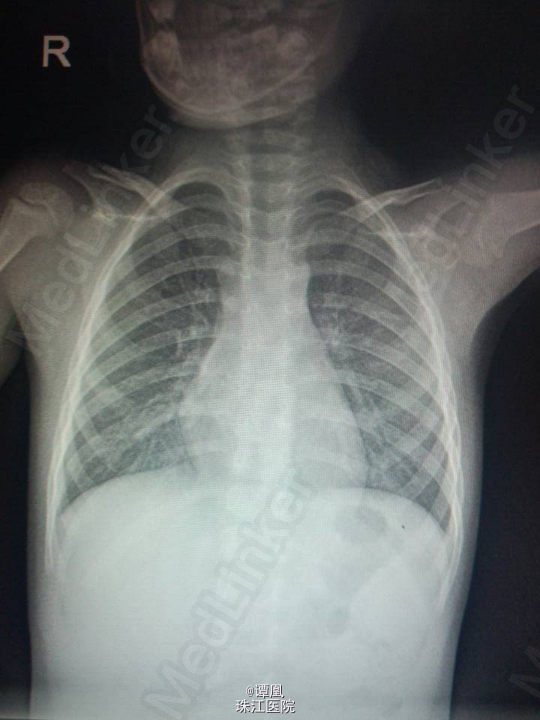

患儿女,3岁 主诉:咳嗽2天 现病史:患儿于昨日无明显诱因出现咳嗽,轻咳,伴流涕,无气喘,在当地医院查血常规示白细胞升高,遂到我院门诊输液“氟氯西林”两天,效果欠佳,今晨咳嗽加重,阵发性,无痰,无气喘,呕吐一次,量少,为胃内容物,无发热,自起病以来患儿精神饮食睡眠一般,大小便正常,体力体重无明显改变。 既往史:近两月反复咳嗽,发热,在中医药治疗,余无特殊。

查体:生命体征平稳,查体无特殊。 辅助检查:胸部X线示双肺野见散在模糊点片影。

诊断:支气管肺炎 处理:1、完善血尿常规、肝肾功能、血培养等;2、给予昆柏、益保世灵等抗感染治疗;3、给予抗病毒等对症支持治疗;4、密切关注病情变化并及时处理。